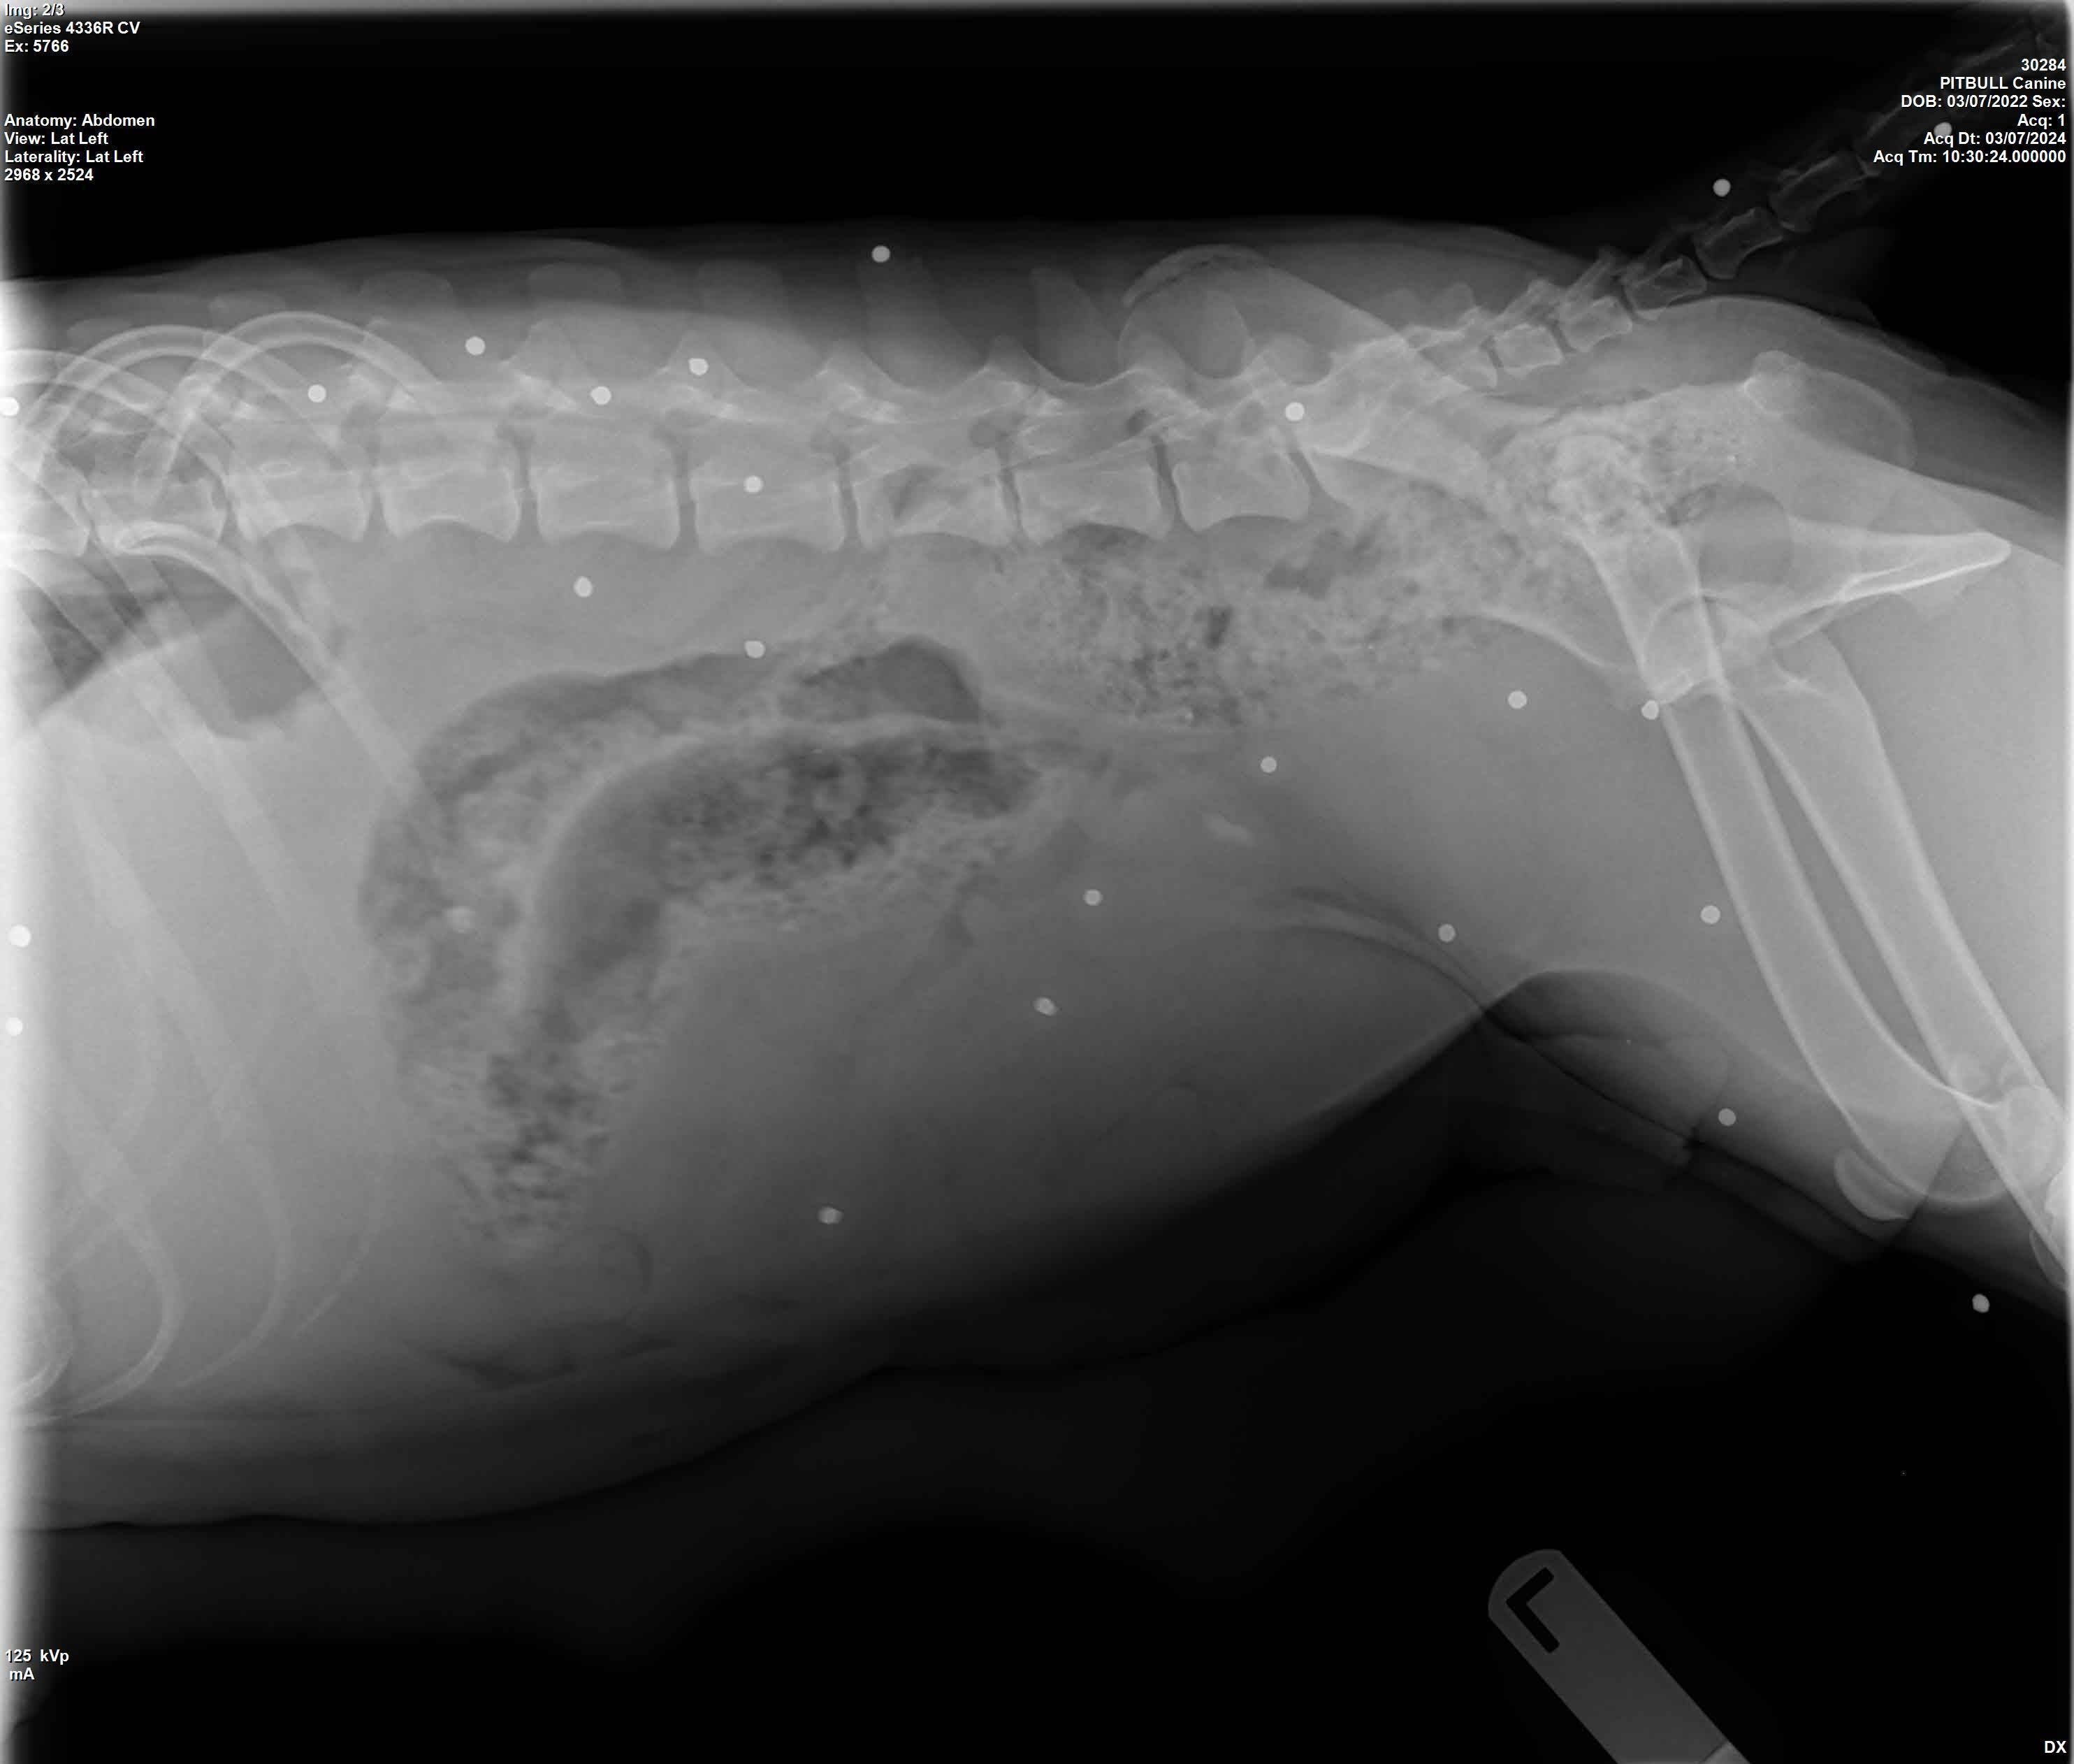

The nine pups remaining under MVAS care received exams, vaccines and dewormers. Priscilla was sent to the vet for an exam and x-ray, which revealed that the young dog had more than 25 BB pellets lodged under her skin from being shot multiple times.